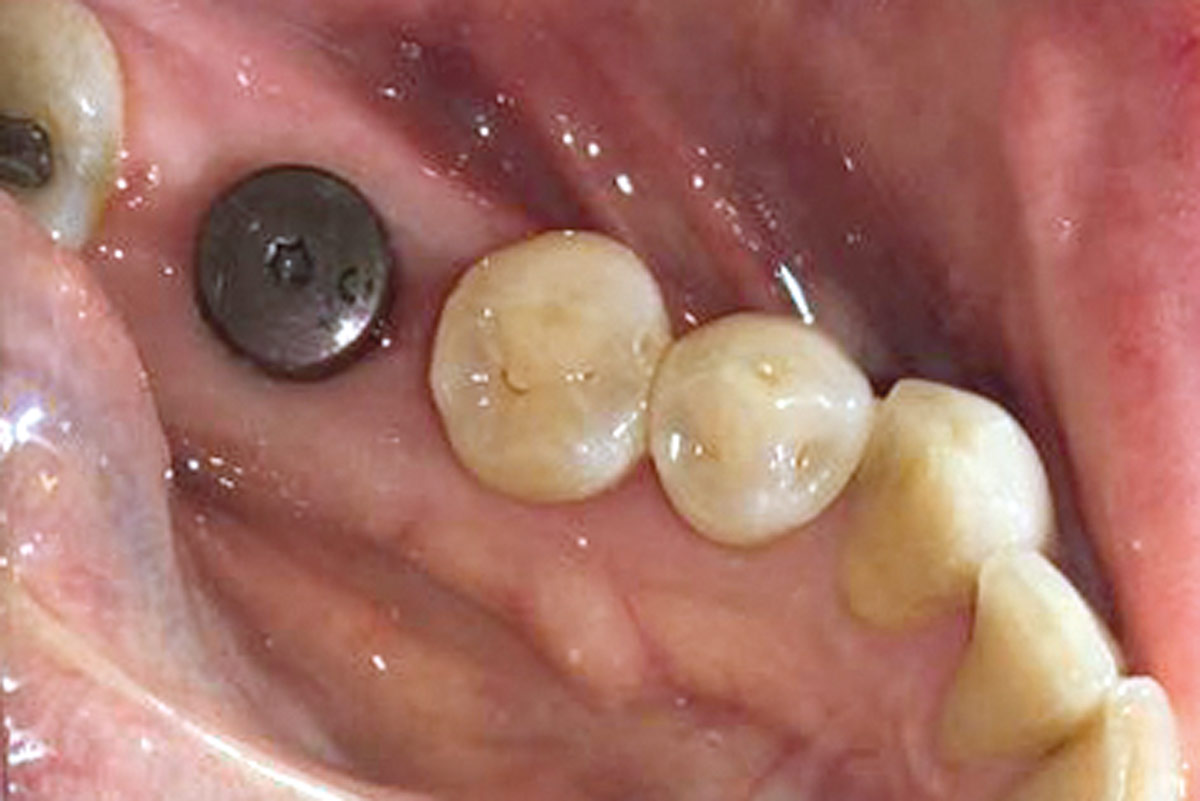

Immediately placed implant covered with permamem®. permamem® passively immobilized by sutures and intentionally left exposed to the oral cavity.